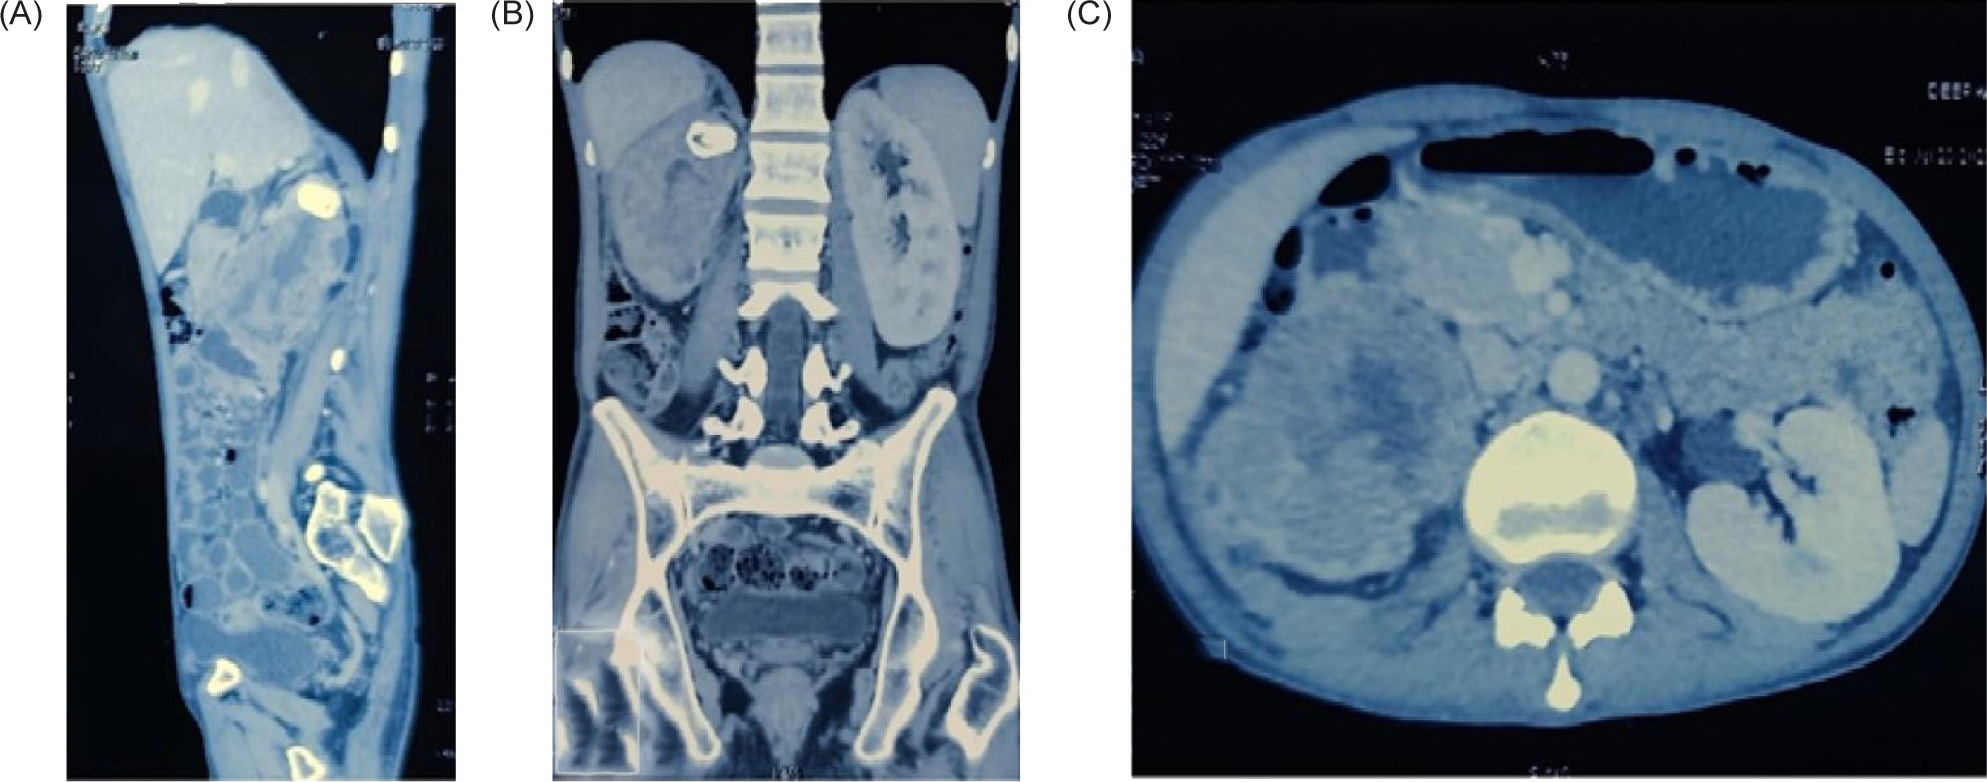

Examination of both testes revealed normal findings. Abdominal and pelvic computed tomography (CT) scan revealed a deformed right kidney with soft tissue mass of size 11 × 7 × 6.5 cm in the mid and lower pole extending to the hilar region, with compression of pelvicalyceal system and an upper pole calculus of size 2.4 × 1.2 cm (Figure 1). Post contrast examination showed inhomogenous enhancement of the mass with no evidence of contrast excretion from the kidney. The CT of his chest showed no nodules or pulmonary metastases. The patient underwent a right open radical nephrectomy with lymph node dissection. Intraoperative, a 15 × 7 cm right renal mass was noted infiltrating the psoas muscle, duodenum, and liver. Additionally, a few enlarged retroperitoneal lymph nodes were also noted. The procedure involved the excision of the infiltrated mass in the duodenum with subsequent repair of the duodenum and the creation of feeding jejunostomy and retrograde duodenostomy (Figure 2). The histopathology report indicated a high-grade malignant NSGCT. Additionally, the submitted lymph nodes tested negative for malignancy. Immunohistochemistry performed showed diffuse positivity in the tumor cells for OCT-3/4 of moderate to strong intensity; patchy cytoplasmic granular staining for alpha-fetoprotein (AFP) was noted mostly in the solid areas—focal cytoplasmic granular positivity for alpha-methylacyl-CoA racemase (AMACR) and focal membranous positivity for CD10—and were negative for PAX-8, CD117, GATA-3, Vimentin, and CD30 (Figures 3 and 4). There was no loss of expression of INI-1; focal incomplete membranous staining for CK-7 and CK-20 was noted in the papillary areas (Figure 5).

Figure 1: Sections of CECT abdomen (A) sagittal, (B) coronal, (C) axial. Suggestive of a deformed right kidney with soft tissue mass the size of 11 × 7 × 6.5 cm in the mid and lower pole extending to the hilar region with the compression of pelvicalyceal system and an upper pole calculi the size of 2.4 × 1.2 cm. Post contrast examination showed inhomogenous enhancement of the mass with no evidence of contrast excretion from the kidney.